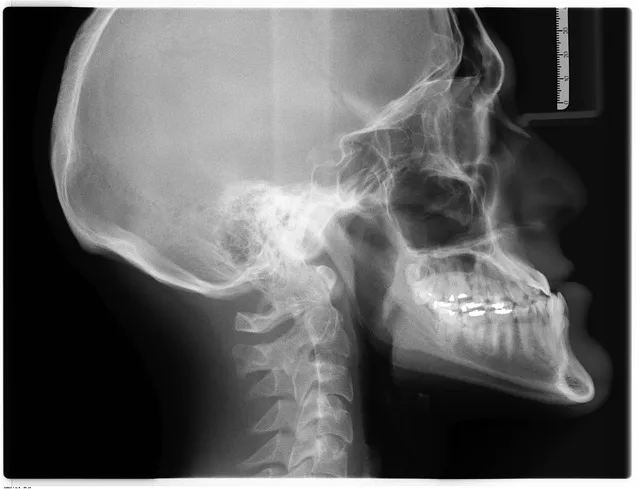

Kraniogram